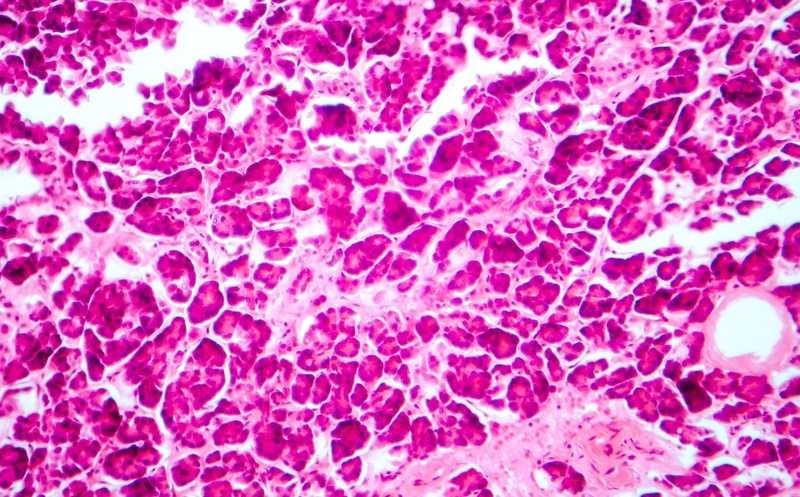

Сахарный диабет 2 типа (СД2) — это мультифакторное хроническое заболевание, связанное со сниженной чувствительностью к инсулину и дисфункцией бета-клеток островков Лангерганса (ОЛ). Молекулярные и клеточные механизмы, лежащие в основе СД2, до сих пор не до конца ясны. Недавние исследования выявили несколько микроРНК, уровень экспрессии которых изменен у пациентов с диабетом, что позволяет предположить их участие в патофизиологии заболевания. Один из подходов к дальнейшему изучению проблемы — сопоставление данных об экспрессии мРНК и микроРНК в островковых клетках. Это поможет определить генетические сигналы, общие для локусов количественных признаков экспрессии (eQTL) и риска СД2.

Ученые из США опубликовали в PNAS крупнейший на сегодня анализ экспрессии микроРНК в клетках ОЛ в контексте СД2. Они секвенировали микроРНК в 63 образцах островковых клеток; 59 из них были получены от доноров с нормальной толерантностью к глюкозе, 4 — от пациентов с диабетом. Для части образцов также провели генотипирование и РНК-секвенирование. При анализе исследователи оценивали корреляция экспрессии обнаруженных микроРНК с рядом фенотипических признаков, таких как индекс массы тела, уровни глюкозы, гликированного гемоглобина и инсулина в крови.